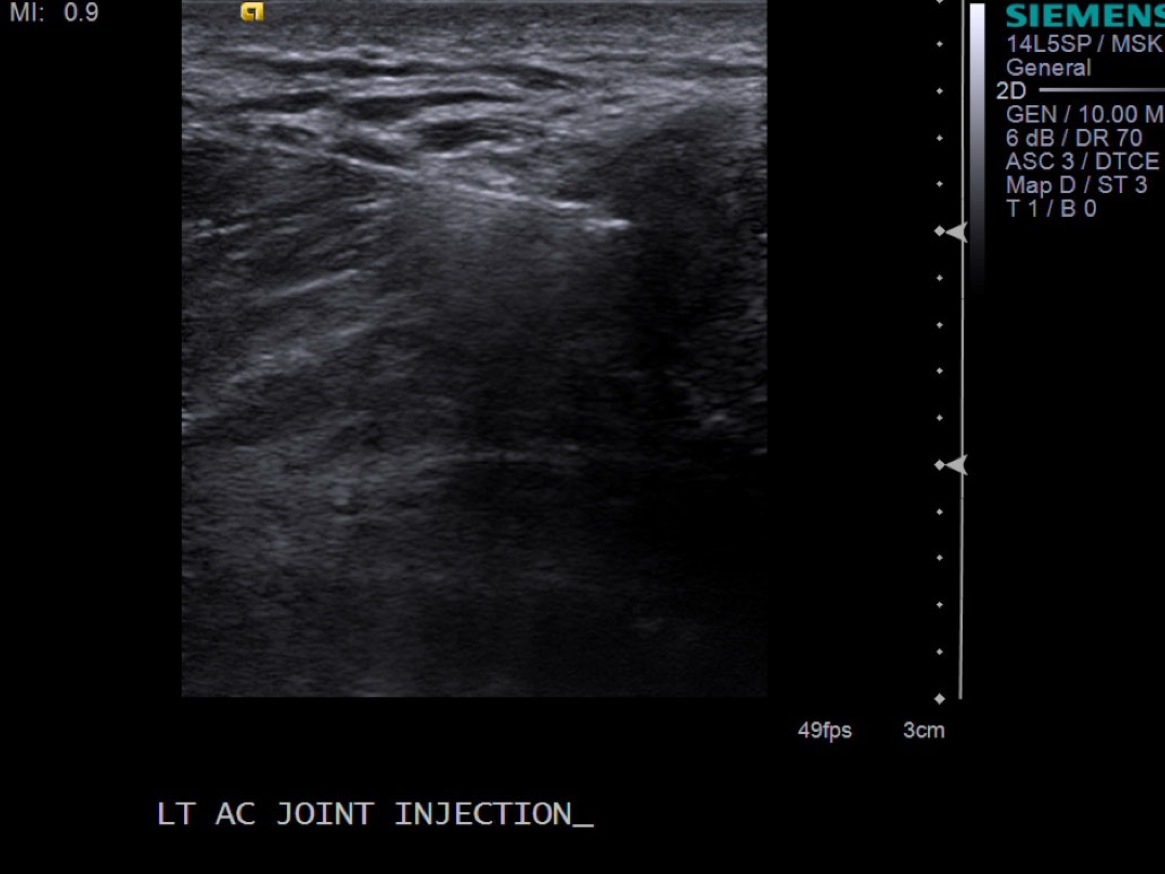

8. Pull needle out and follow standard post-procedure protocol with cleaning off the skin and placing a bandage. Post procedure transverse images demonstrating distention of the joint with steroid and anesthetic.